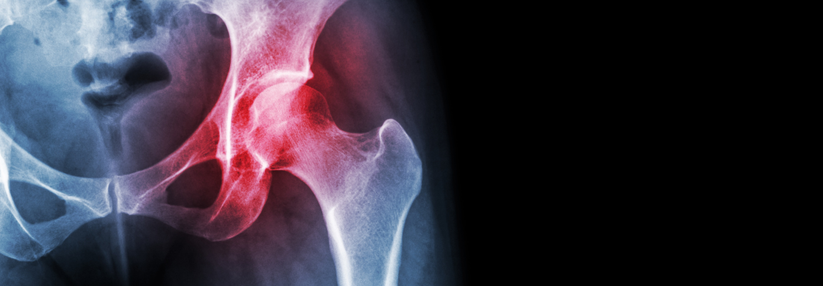

Osteoporose: Nur jeder Fünfte wird leitliniengerecht behandelt

Die Versorgung von Osteoporose-Kranken in Deutschland lässt zu wünschen übrig. Ein pragmatischer und alltagstauglicher Algorithmus soll die Lage…